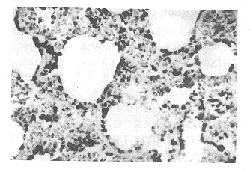

图1 照后3月,大鼠肺组织TGFβ1

免疫组化染色呈现强阳性反应

(ABC法 ×400)

通过采用免疫组织化学的方法,我们对各取材点的大鼠肺组织,进行了TGFβ1、TGFβ2、bFGF、PDGF-A和TGFβRI在其中表达变化规律的研究。结果表明,正常大鼠肺组织即有TGFβ1和TGFβRI的弱表达,照射动物肺脏TGFβ1的表达于照射后2周开始增高,于第4周明显增强,从第8周直到3个月表达水平最高,之后开始下降,但仍维持比正常对照较高水平的表达(图1、2)。肺脏表达TGFβ1的部位主要是支气管上皮细胞,肺泡巨噬细胞、肺泡上皮细胞、支气管和血管平滑肌细胞以及成纤维细胞等。TGFβ2 的表达变化规律除了比 TGFβ1稍弱外类似于TGFβ1。TGFβRI表达增强的时间比TGFβ1稍晚,于第8周开始增强,直到1年仍保持较高水平的表达。对于bFGF和PDGF-A,我们也进行了照射后3个月以内各时间点大鼠肺组织中表达的研究,结果表明,这两种生长因子在照射后大鼠肺组织中的表达也增强,其中在照射后2~3个月表达水平明显增高。